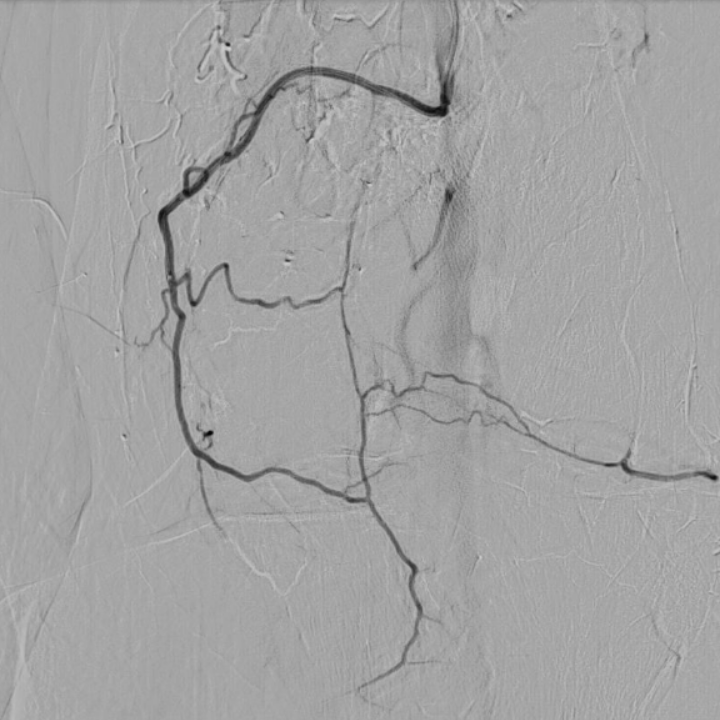

case of the day - 09.02.2026

Kniegelenk

Hier sehen Sie die Bilder vor und nach der Behandlung bei chronischen Kniegelenksbeschwerden. Sehr deutlich ist die geringere Kontrastmittelaufnahme nach Behandlung als Hinweis der verringerten Durchblutung der entzündeten Bereiche zu sehen.

Arteria genicularis inferior lateralis - vor Behandlung

Arteria genicularis inferior lateralis - nach Behandlung